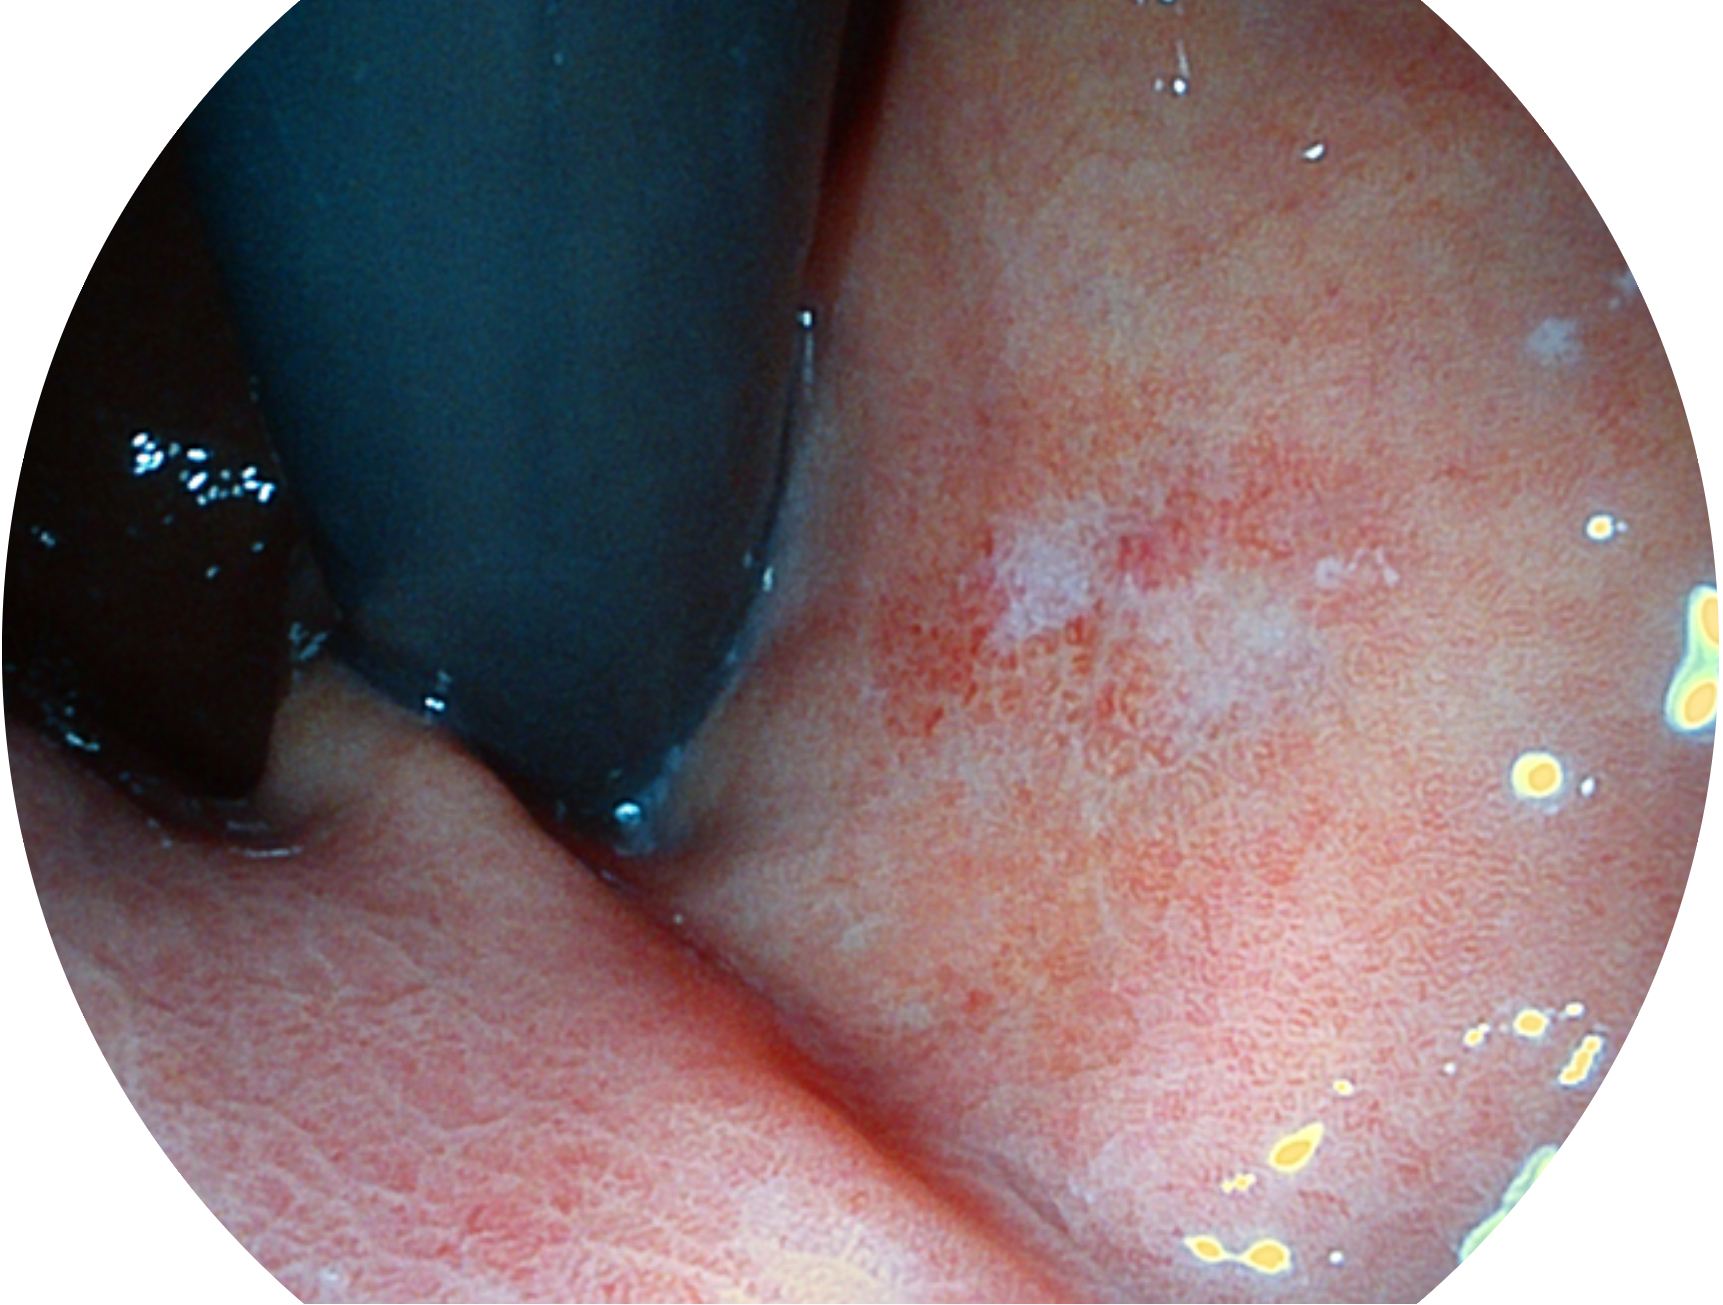

• 白光图像 SFI图像